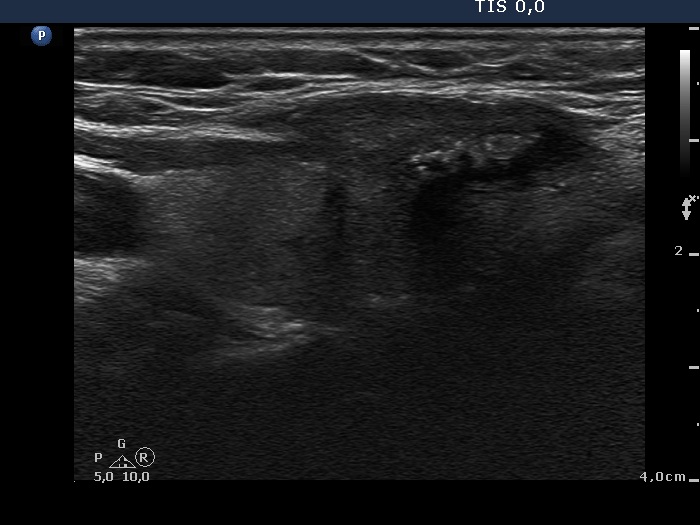

Ultrasonography. The right lobe was echonormal and contained several small, insignificant lesions. There was a hypoechogenic, irregularly shaped mass in the lower half of the left lobe. The lesion had a rigged, echonormal core which showed bright hyperechogenic granules. There were multiple incomplete acoustic shadows dorsal to the lesion which was avascular.